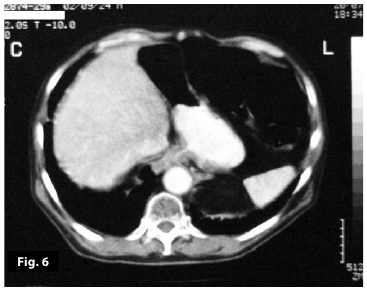

Figure6